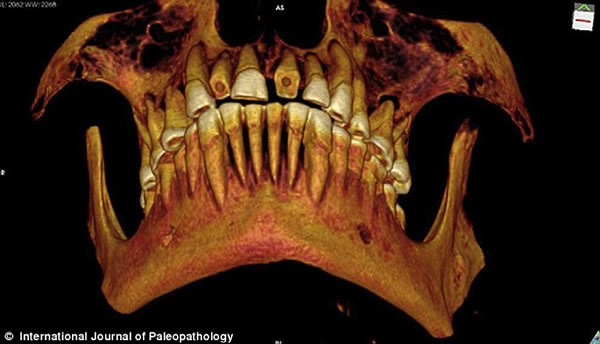

研究人员通过CT扫描图片观察木乃伊的口腔,并重建了一张显示磨损门牙的3D图。

《古病理学国际期刊》的文章称,来自加拿大西安大略大学的安德鲁·韦德利用一种新型高分辨率CT仪扫描木乃伊的牙齿和身体,并且根据扫描片重建了3D图以进行更为细致的研究。从CT扫描片可以看到,木乃伊的一颗牙齿龋洞里塞着一块亚麻布团。这块亚麻布之前可能经过无花果汁液或雪松油等药物的浸泡,随后被塞入下颚第一、二颗臼齿中间,也就是最大、也是最疼的龋洞里。这么做既能起到抵挡食物残渣进入龋洞的屏障作用,又能利用亚麻布上的药物缓解疼痛。